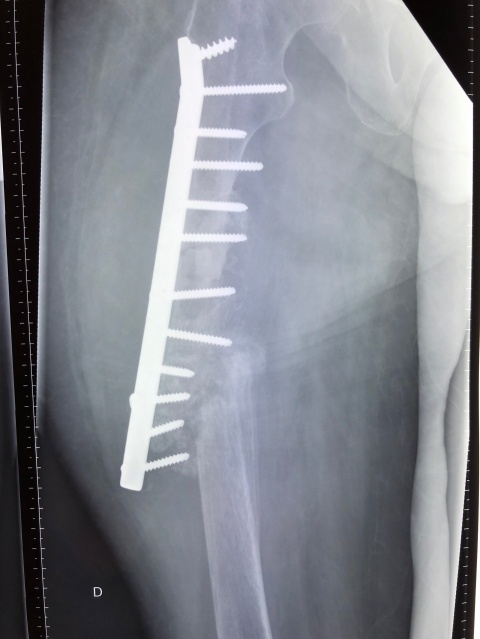

Die Fortbewegung war nur krabbelnd und hüpfend möglich. Im Röntgenbild sah man Residuen der Tibiakopffraktur sowie eine Verkalkung im Bereich der dorsalen Kapsel. Es erfolgte eine Arthrolyse des Kniegelenkes ventral und dorsal, gefolgt von einer redressierenden Gipsanlage (Abb. 4), wodurch die Beugekontraktur auf eine ROM von 0 – 20 – 110° erweitert werden konnte. Die verkürzte Muskulatur wird jetzt physiotherapeutisch behandelt und der Patient war zum Abschluss der Behandlung gehfähig. Ein zweiter wesentlicher Part der chirurgischen Tätigkeit stellte die Revision unzureichender Heilungsergebnisse dar. Die Ursachen hierfür waren heterogen. Fehlende Verfügbarkeit geeigneten Materials und unzureichende Nachbehandlung standen hierbei im Vordergrund. So auch bei unserem 2. Fallbeispiel, einer 51-jährigen Dame, die vor einem Jahr eine Oberschenkelfraktur erlitten hatte und mittels Nagelosteosynthese versorgt wurde. Dieser wanderte proximal aus und bei bestehender Pseudarthrose erfolgte eine Plattenosteosynthese. Leider wurde zur postoperativen Immobilisation eine Mecron-Schiene in Kombination mit einem Rollstuhl gewählt, bei dem leider keine Abstützung des Beines möglich war. So hebelte die Schiene direkt am Ende der Platte und es kam zu einer Anschlussfraktur (Abb. 5) oberhalb der Platte. Diese wurde durch uns revidiert und mit einer DHS mit 16 Löchern ersetzt (Abb. 6). Hierunter konnte letzten Endes eine ausreichende Stabilisierung erreicht werden.